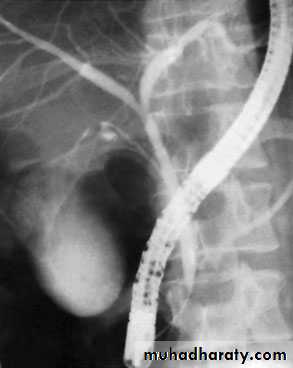

51NORMAL ERCP

Endoscopic retrograde cholangiopancreatographydemonstrating stone obstructing the common bile duct (arrow